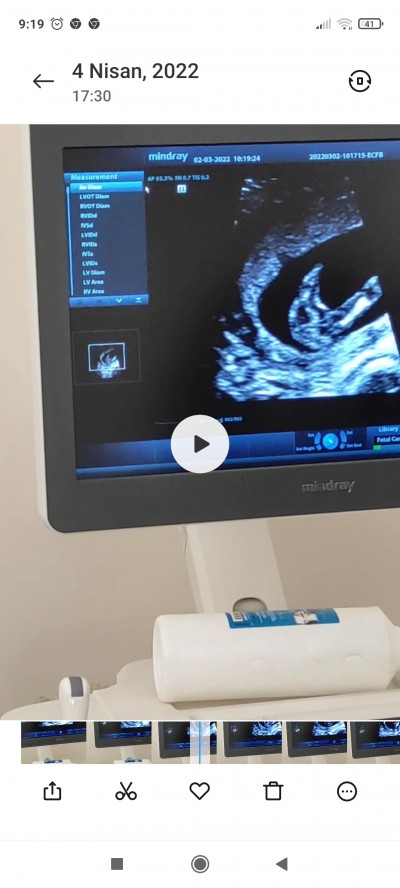

İki bacağının arası bu resimde 15 haftalık videosunda var ama ben atamadım

Gebelik haftası 19 ama videoda 15

Doktorum 13 haftalıkken erkek dedi 15 haftalıkken bu resimdeki işte ordada bu kız ama kesin bişey diyemem dedi kafam çok karışık

Hani bos duruyor cikıntı göremedim kız gibi cnm saglıkla gelsin insallah